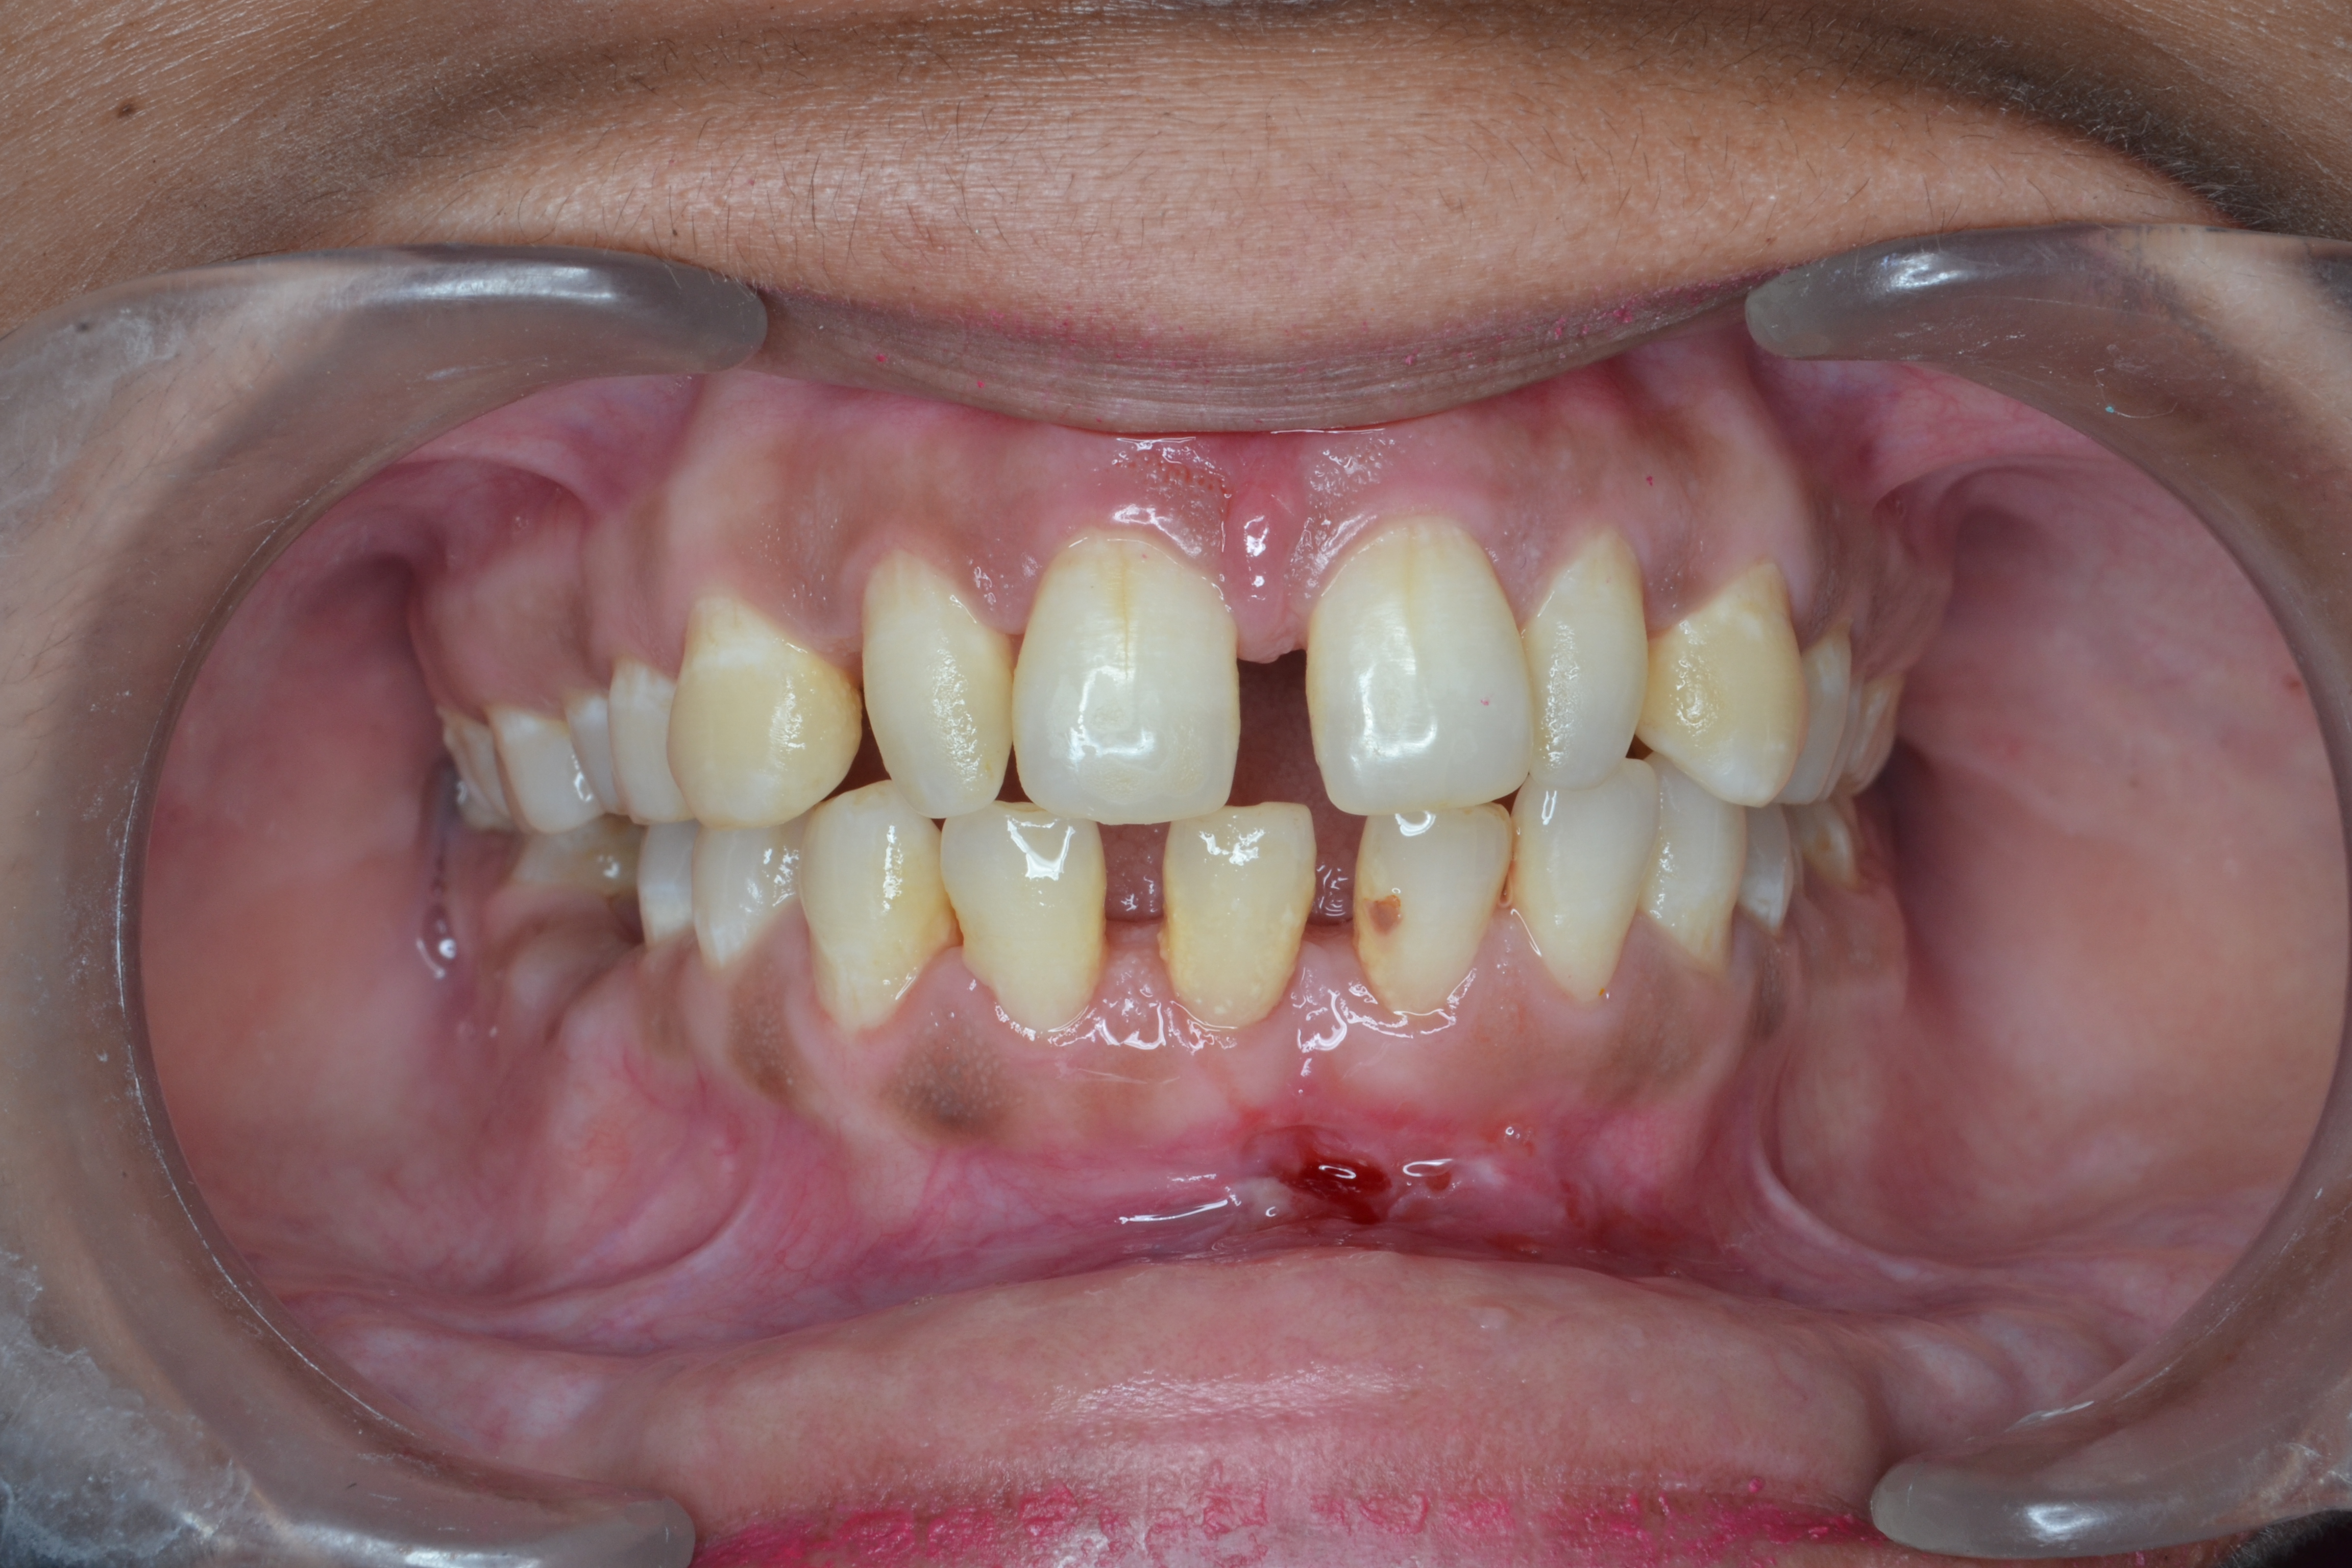

After/Before

See stunning smile transformation before and after

Before After